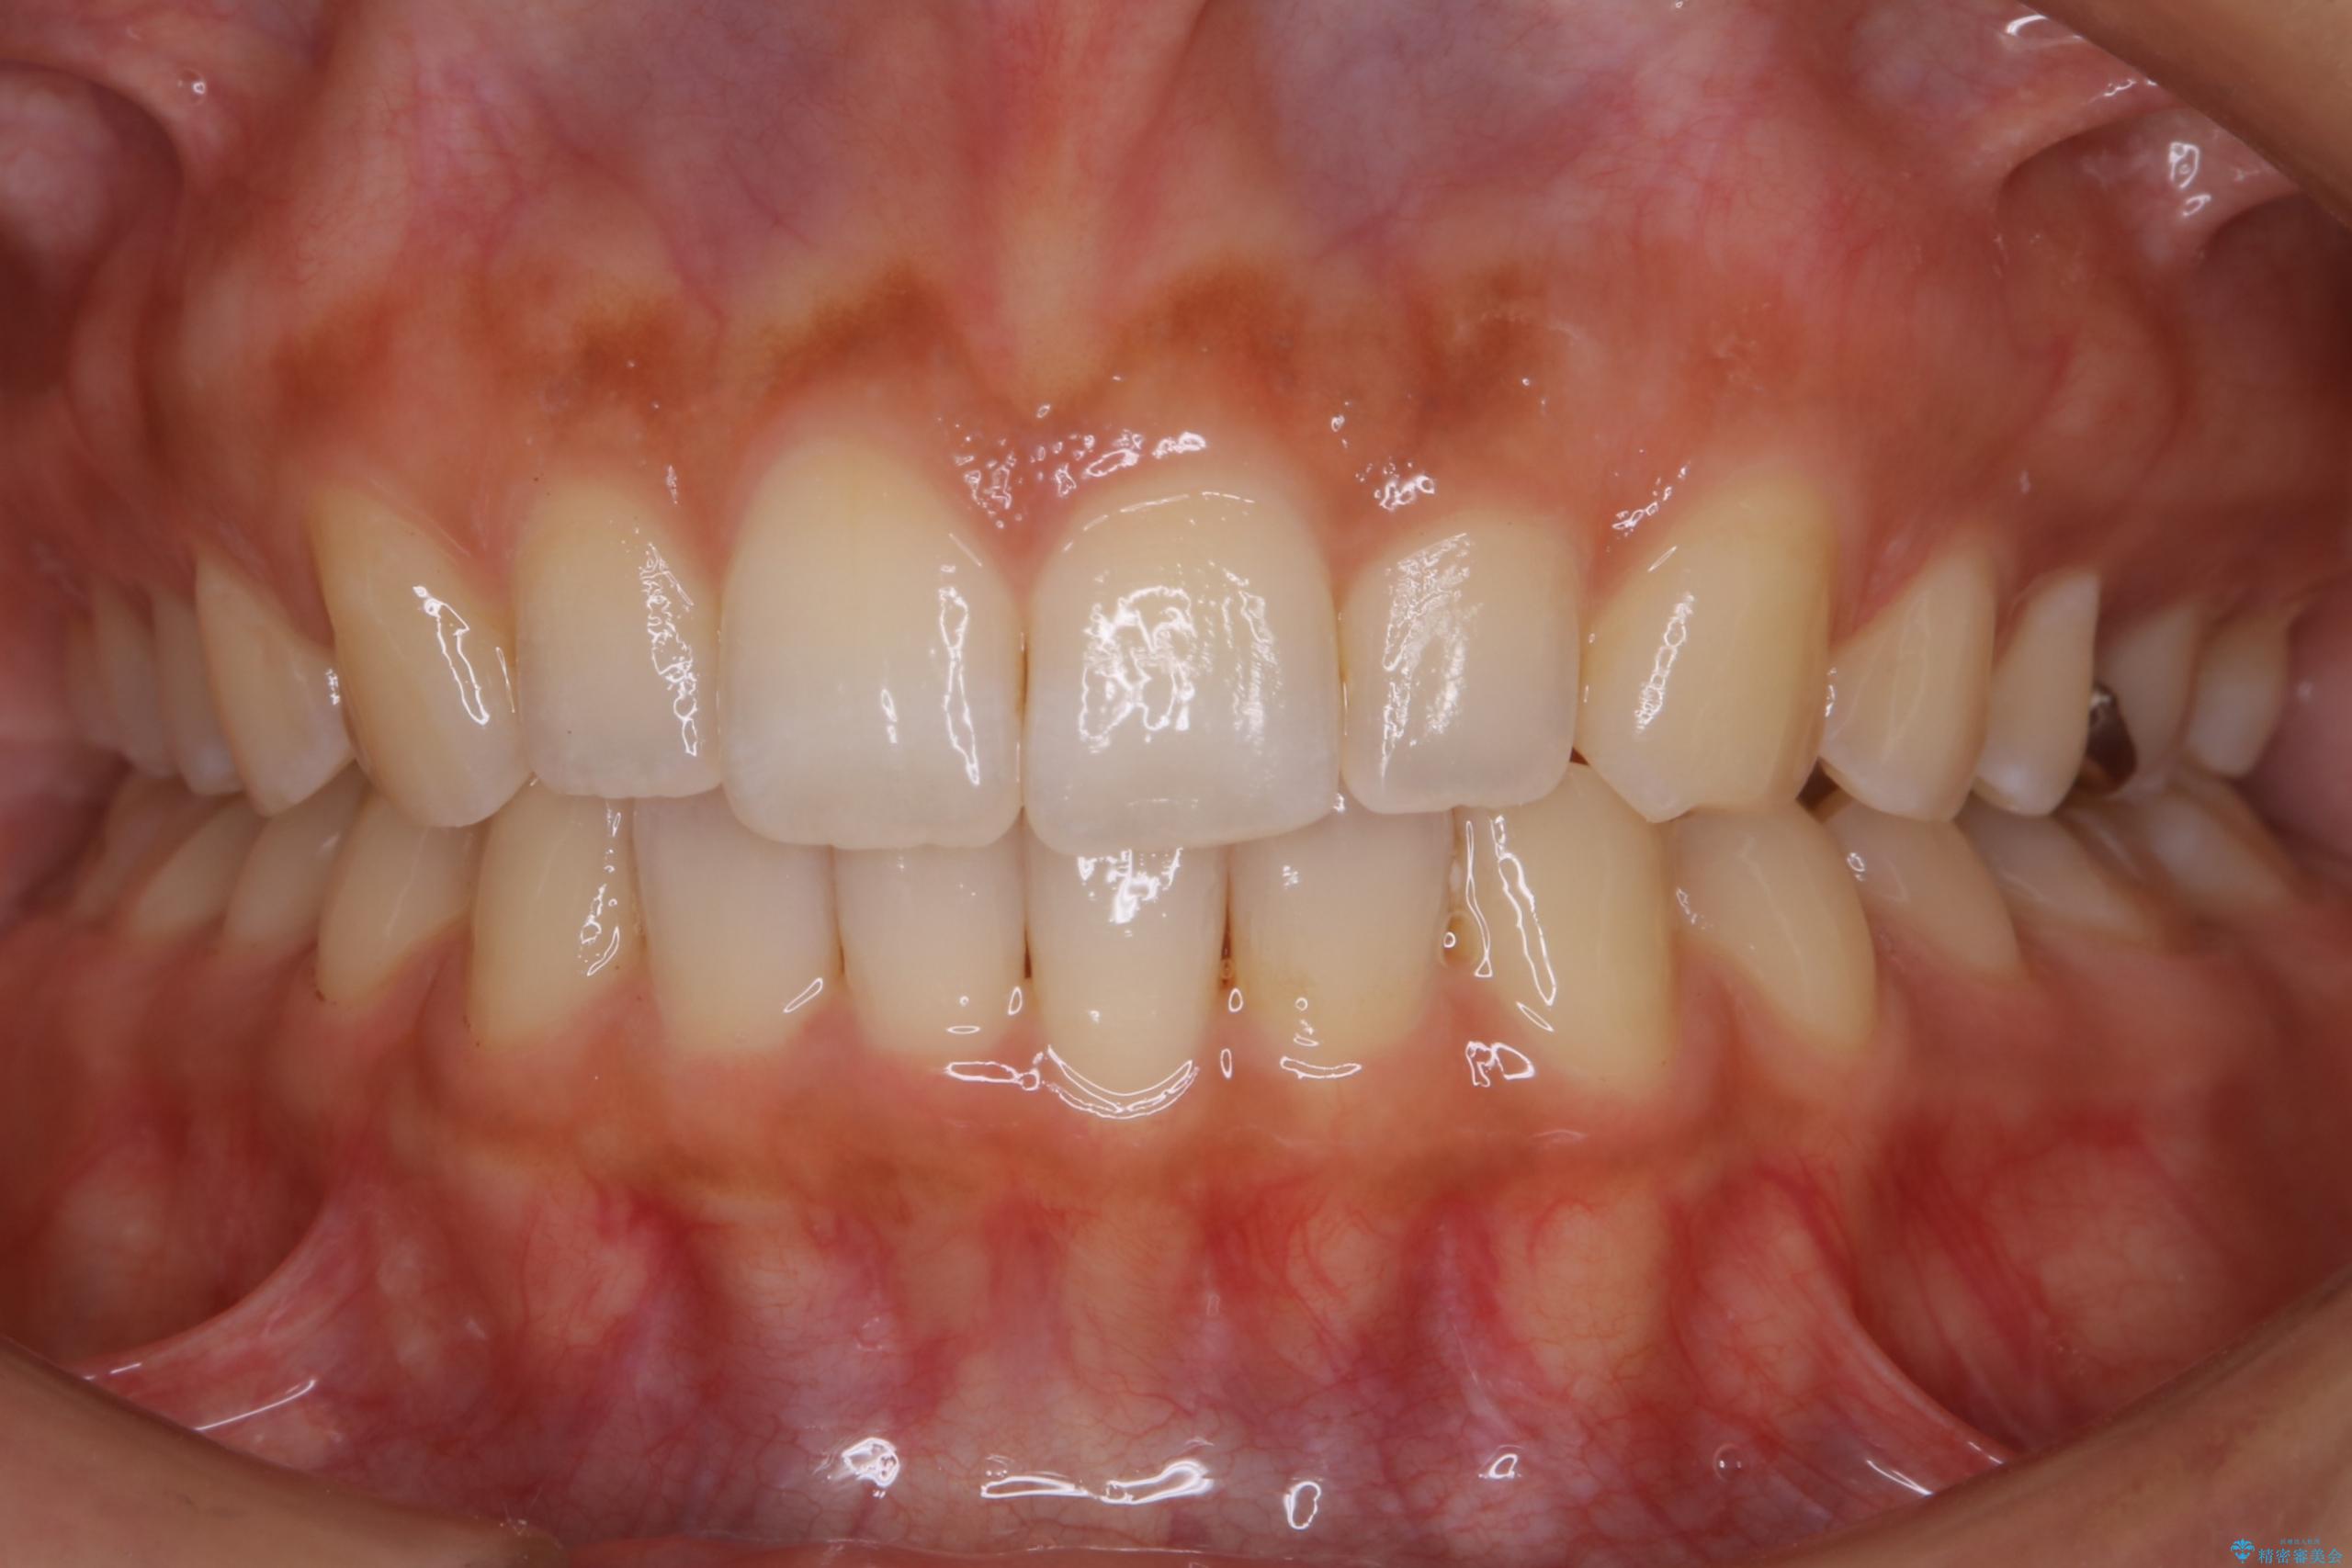

下の歯列よりも上の歯列が前に出ている状態を治すため、マウスピース矯正に加え、患者様にゴムかけのご協力をいただきました。その結果、ガタつきが改善し、上下の噛み合わせが適切な位置で合うようになりました。